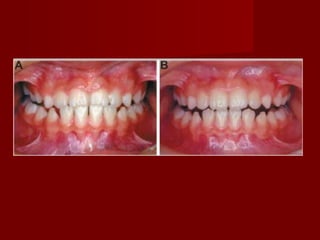

 Crossbite caused by mandibular shiftCrossbite caused by mandibular shift

should be treated as soon as they areshould be treated as soon as they are

discovered.discovered.

– An uncorrected mandibular shift can produceAn uncorrected mandibular shift can produce

undesirable soft tissue grown modification.undesirable soft tissue grown modification.

– Occlusal analysis for premature contact andOcclusal analysis for premature contact and

functional mandibular shift.functional mandibular shift.